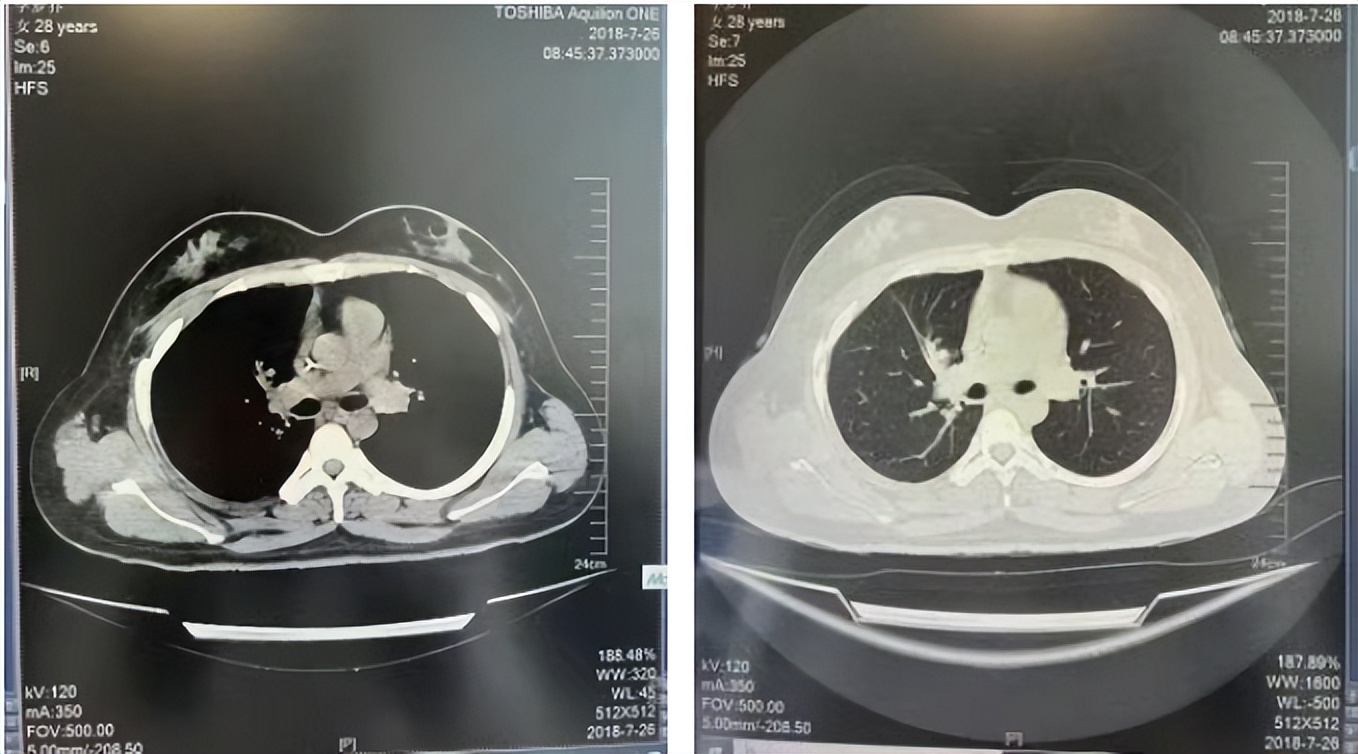

2016年1月复查CT提示支气管截断可见新发小结节,一线治疗采用培美曲塞+DDP方案化疗4周期(培美曲塞3.36,DDP 480mg)。化疗后复查胸部CT:右肺见不规则结节样影,最大层面大小约19mm*8mm,较前比较明显增大,疗效评估PD。2017.3-2017.4予单药多西他赛化疗3周期,疗效评估SD。2018年5月末复查CT提示结节较前增大,评效为PD,2018年6-10月予多西他赛+CBP化疗4周期,疗效评估SD。2022年5月患者出现活动后气短,复查胸部CT示右肺膨胀不良;右侧胸腔积液增多。胸腔积液包埋病理示符合肺腺癌细胞。行NGS基因检测:EML4:exon13-ALK:exon20融合。PD-L1(克隆号22C3)TPS<1%。

2018.07

2022.05

2022.08

2023.05

2024.12